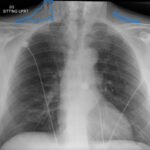

Subcutaneous emphysema (SE) is a rare but significant complication following dental procedures characterized by the presence of air in the subcutaneous tissue. This case report presents a 67-year-old male who developed right-sided facial swelling after tooth extraction, a procedure executed with high-power dental tools. Clinical findings included facial swelling and crepitus with no lip involvement, differentiating SE from an allergic reaction and hematoma. Diagnostic imaging through computed tomography (CT) and chest X-ray confirmed SE, showing diffuse subcutaneous air in facial and neck soft tissues. Initial management in the emergency department (ED) involved administration of antihistamines, corticosteroids, antibiotics, and otolaryngology (ENT) consultation with close monitoring for airway compromise. This case underscores the importance of including SE in differential diagnoses for post-dental procedure swelling, the effectiveness of CT imaging in SE identification, and the importance of early detection and treatment to prevent severe complications like respiratory and cardiac issues.